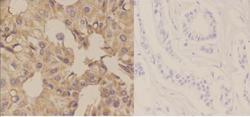

Immunohistochemistry

A14634-1 IHC